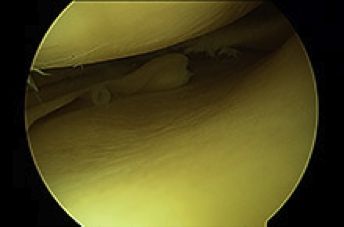

LESIONES MENISCALES

Los meniscos son dos fibrocartílagos de la rodilla que se sitúan entre el fémur y la tibia para aumentar la congruencia articular, facilitar el movimiento y favorecer el reparto de cargas de un hueso al otro. Uno se sitúa en la parte interna, es el menisco interno. Tiene forma de "C" y no es muy móvil. El menisco externo es más cerrado en forma más parecida a una "O", y tiene mayor movimiento hacia delante y detrás cuando la rodilla se flexiona y extiende. En su parte posterior deja un ojal para el paso del tendón poplíteo. El menisco externo es más ancho y se sitúa sobre un platillo tibial convexo, no cóncavo como el interno. En algunos pacientes este menisco externo recubre completamente o casi completamente el platillo y recibe el nombre de menisco discoideo.